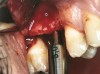

A full-thickness mucoperiosteal flap was raised, and alternating osteotomes were used to prepare the implant site. After achieving a length of 7 mm (Figure 7A and Figure 7B), heterologous bone graft was implanted and the osteotome sequence was repeated. The implant showed primary stability.

Figure 7A and Figure 7B Alternating osteotomes with variable conicity used to perform the alveolar remodeling in the area of tooth No. 15.

Figure 7a  Alternating osteotomes with variable conicity used to perform the alveolar remodeling in the area of tooth No. 15.

Figure 7a

Figure 7b  Alternating osteotomes with variable conicity used to perform the alveolar remodeling in the area of tooth No. 15.

Figure 7b